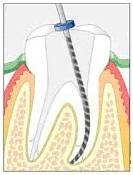

Bei einer Wurzelbehandlung wird das Zahnmark (Pulpa), also das Weichgewebe eines Zahnes vollkommen bis zur Wurzelspitze (Apex) entfernt (siehe dazu auch Kapitel Endodontie mit Laser). Die durch die Ausräumung der abgestorbenen Pulpa entstandenen Hohlräume im Zahninneren werden dann mit einer sterilen Wurzelfüllpaste abgefüllt.

Das Ziel einer Wurzelbehandlung ist die Erhaltung des Zahnes, wobei er schmerzfrei, keimfrei und entzündungsfrei funktionstüchtig sein muss. Der Weg dazu ist die sterile Wurzelfüllung aller Wurzelkanäle bis hin zur Wurzelspitze.

Der Zahn besteht aus einer Zahnkrone und einer Wurzel, die mit einer oder mehreren Wurzelspitzen im Knochen verankert ist. Durch diese Wurzelspitzen treten die Blutgefässe und die Nerven in den Zahn ein - sie sorgen für die Versorgung des Zahnes und für das Temperatur- und Berührungsempfinden. Bei einer Wurzelbehandlung (siehe Kapitel Endodontie) wird das Zahnmark (Pulpa), also das Weichgewebe eines Zahnes, vollkommen bis zur Wurzelspitze (Apex) entfernt. Dies geschieht mittels extrem kleiner und feiner Feilen, welche den Wurzelkanal erweitern und es erlauben, die Pulpa auszuräumen.